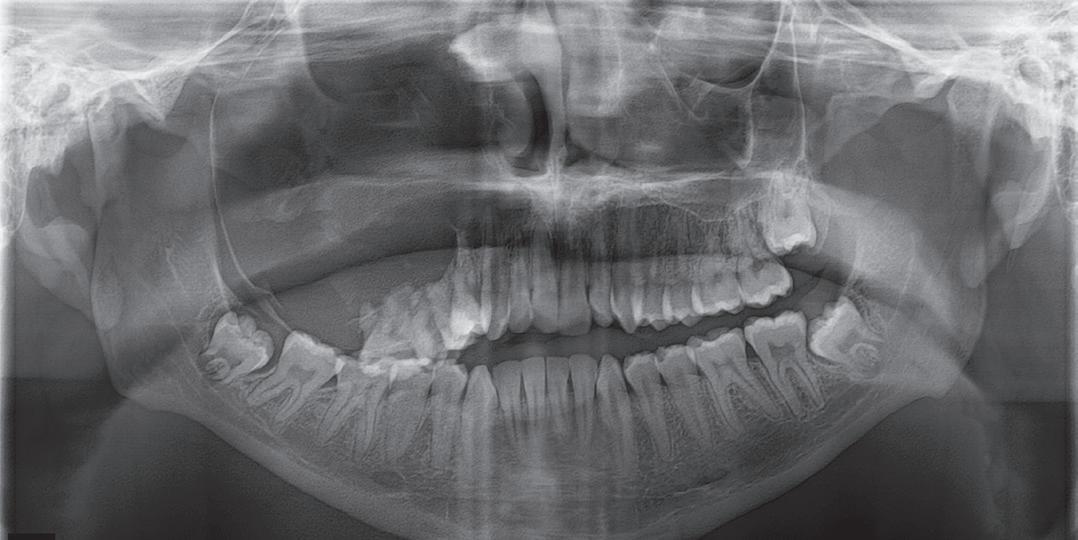

The surgery is called Jaw in a Day, and James was the first patient in Tennessee and the Mid-South to undergo it. Performed by a multidisciplinary team of surgeons from the UT Health Science Center, the procedure involved removing the tumor, building the facial bones, eye socket, and jaw out of James’s leg bone, and installing dental implants and prosthetic teeth—all within one day.

In James’s case, timing was on his side. He arrived as a patient when the surgeons felt confident they were ready to perform the surgery for the first time. They confirmed he was a good candidate—considering factors such as his overall health, dental health, and the cause and extent of the jaw problem—and then began the extensive planning process.

Using James’s CT scans, the surgeons created 3D computer models of the skull and the leg bone and essentially performed the surgery virtually. “This allows us to plan the ideal placement of each component and use multiple patient-specific materials, including guides to help with tumor removal, orientation and positioning of the fibula, and orientation of the dental implants within the fibula. It also allows us to have custom, 3D-printed titanium hardware that helps ensure everything fits together seamlessly,” Dr. Wilson says.

The team used the computer models to 3D print life-size replicas of James’s skull to use during surgery. They also built custom cutting slots to guarantee precise cuts while recreating the pieces of the jaw and custom prosthetic teeth that matched James’s natural jawline and bite.